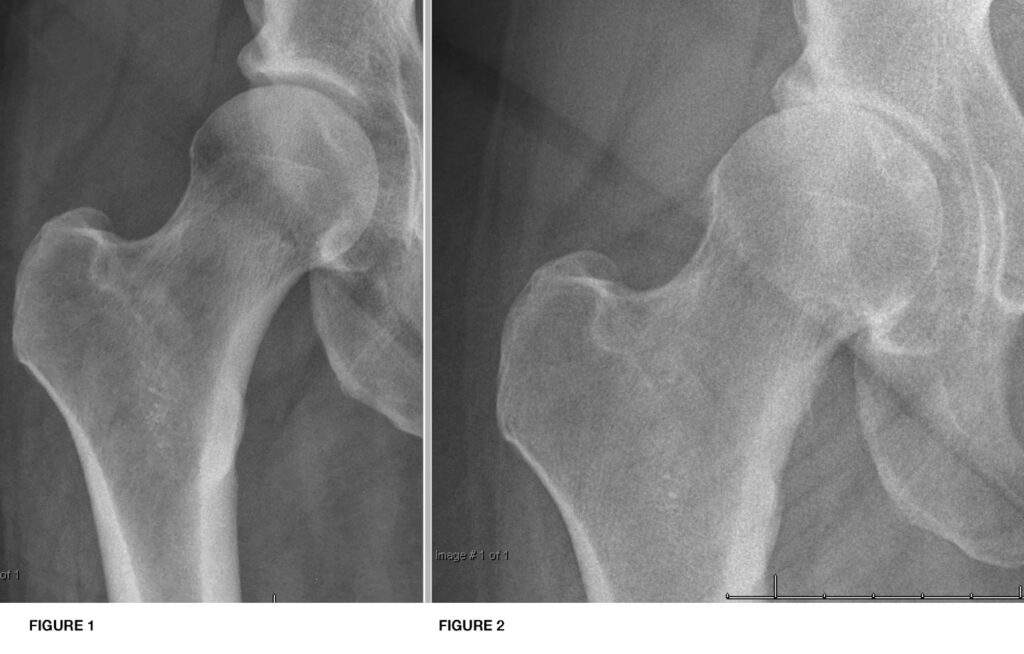

Et røntgenbillede er i bund og grund et todimensionelt billede af kroppens tætte strukturer, primært knogler. Brusk er et blødt væv og er ikke tæt nok til at blive vist tydeligt på et standard røntgenbillede. I stedet ser lægen efter indirekte tegn på, at brusken er beskadiget eller helt forsvundet. Disse tegn er de klassiske kendetegn for slidgigt.

- Forsnævret ledspalte: På et billede af en sund hofte vil der være et synligt mellemrum mellem lårbenets hoved og bækkenets ledskål. Dette 'mellemrum' er i virkeligheden fyldt med brusk. Når brusken slides ned, bliver dette mellemrum mindre. En forsnævret eller helt forsvundet ledspalte er det mest almindelige og tydelige tegn på slidgigt.

- Subkondral sklerose: Når brusken er væk, øges trykket på knoglen nedenunder (den subkondrale knogle). Kroppen reagerer ved at gøre denne knogle tættere og hårdere. På et røntgenbillede ses dette som et hvidere, mere fremtrædende område på knogleoverfladerne i leddet.

- Osteofytter (knogleudvækster): Som en reaktion på den øgede belastning og ustabilitet i leddet, kan kroppen forsøge at 'reparere' skaden ved at danne nyt knoglevæv langs kanterne af leddet. Disse knogleudvækster kaldes osteofytter. De kan ses som små 'spidser' eller udvækster på røntgenbilledet og kan bidrage til smerter og nedsat bevægelighed.

- Cyster: I nogle tilfælde kan der dannes små, væskefyldte hulrum, eller cyster, i knoglen tæt på leddet. Dette er endnu et tegn på den stress, knoglen udsættes for.

- Fri legemer: Små stykker af nedbrudt brusk eller knogle kan brække af og 'flyde' rundt i leddet. Disse kan nogle gange ses som små hvide pletter på et røntgenbillede.